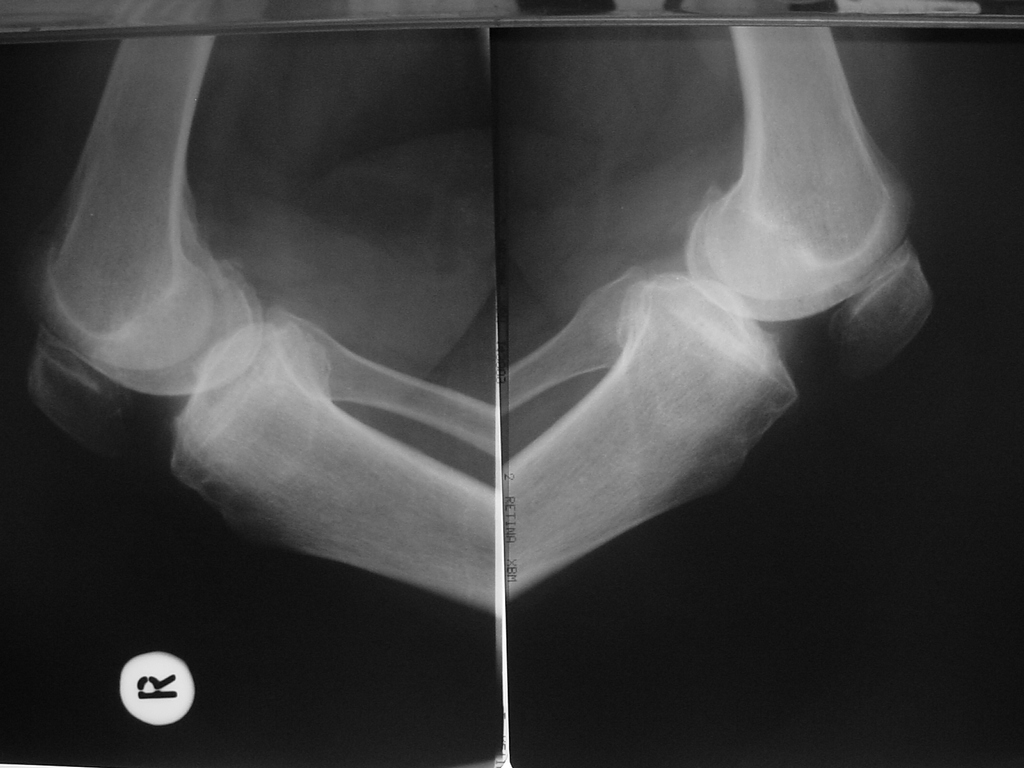

Total Diz Protez ameliyatı kliniğimizde endikasyon dahiline her yaşa başarı ile uygulanmaktadır. Örnek olgumuz: